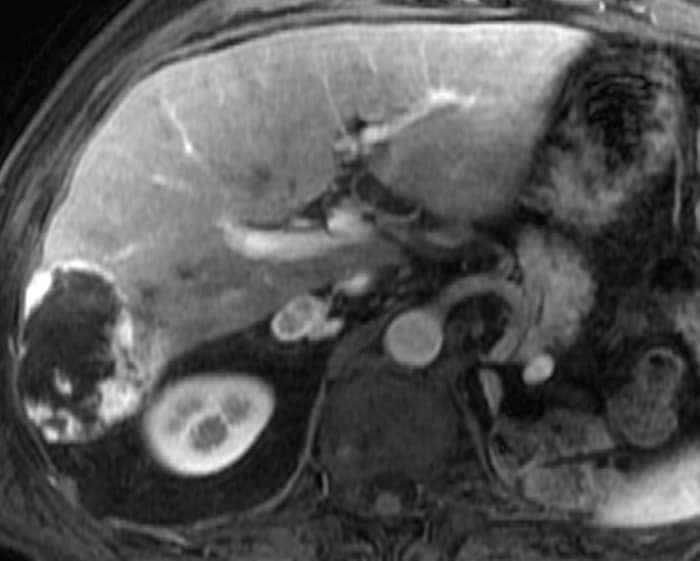

U máu gan

» Thông tin: Nam giới – 70 tuổi.

» Lâm sàng: Tiền sử ung thư thận.